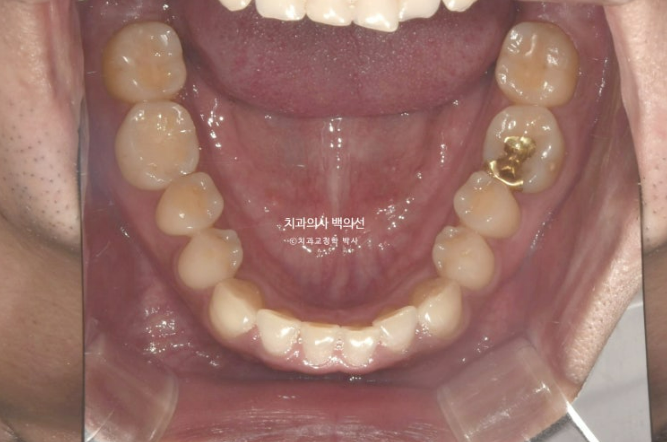

비발치로 아래 전체 치열을 사랑니 공간으로 밀어서 앞니 반대교합을 해소하기로 했습니다.

클리피씨 교정을 선택하셨고 먼저 아래 장치 부착 후 치료를 시작했습니다.

아래에 미니스크류를 심고 사랑니 공간으로 전체치열을 미는 중 입니다.

교합을 맞추기 위해 고무줄도 끼고 25년 4월, 치료시작 1년 9개월 만에 치료를 종료했습니다

철사유지장치까지 부착된 모습입니다.

앞니 거꾸로 물리는 반대교합은 해소가 되었고